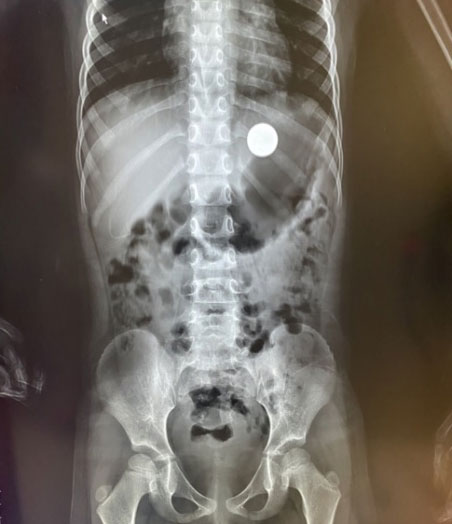

X光检查发现胃中的圆形异物

“在胃底,和食物混在一起了”只见一枚硬币“躺”在胃底,清晰可见,“快,异物网篮”。梁红亮和李杭娟默契配合,把异物网篮插入,在胃内张开,慢慢的伸到硬币旁准备将其套进网篮中。一次、两次、三次,通过不断调整角度,慢慢将硬币全部放进异物网篮中间,再慢慢拉紧收回。梁主任用最轻的力气,缓缓地抽出胃镜,将取出的硬币放在纱布上,大家一直紧绷着的心才放了下来。